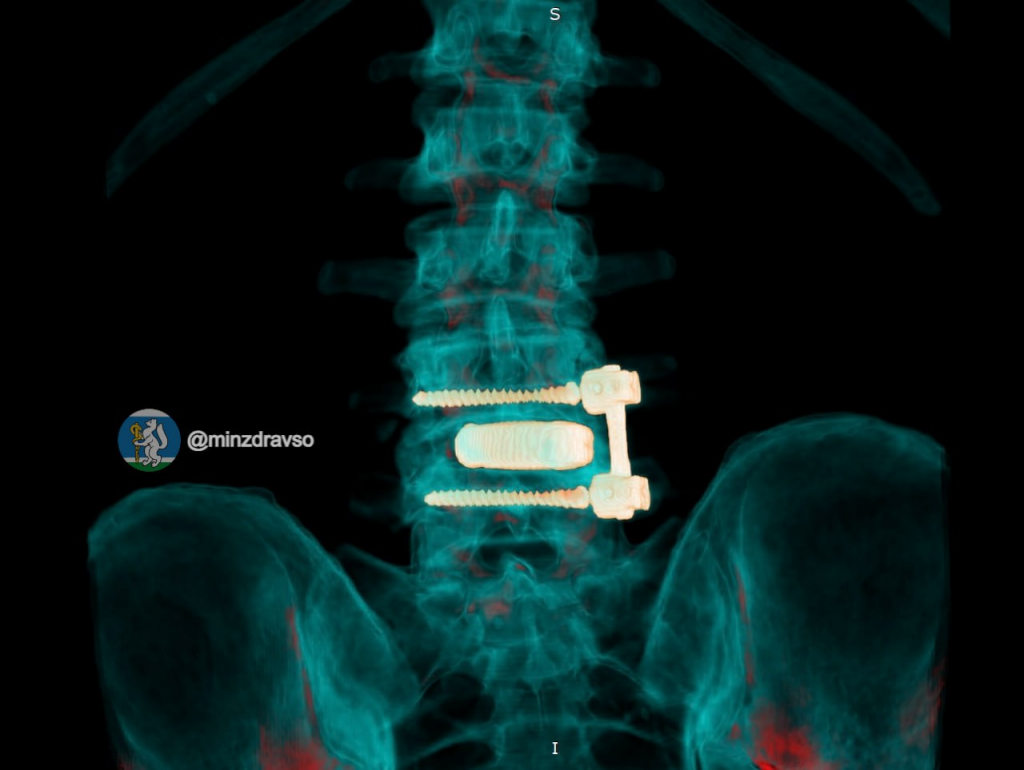

Пациенту установили титановый 3D-имплант, изготовленный по индивидуальным параметрам. Фиксацию выполнили российскими спонгиозными винтами. Уже в первые сутки после операции болевой синдром полностью купировался, пациент самостоятельно встал и начал ходить.